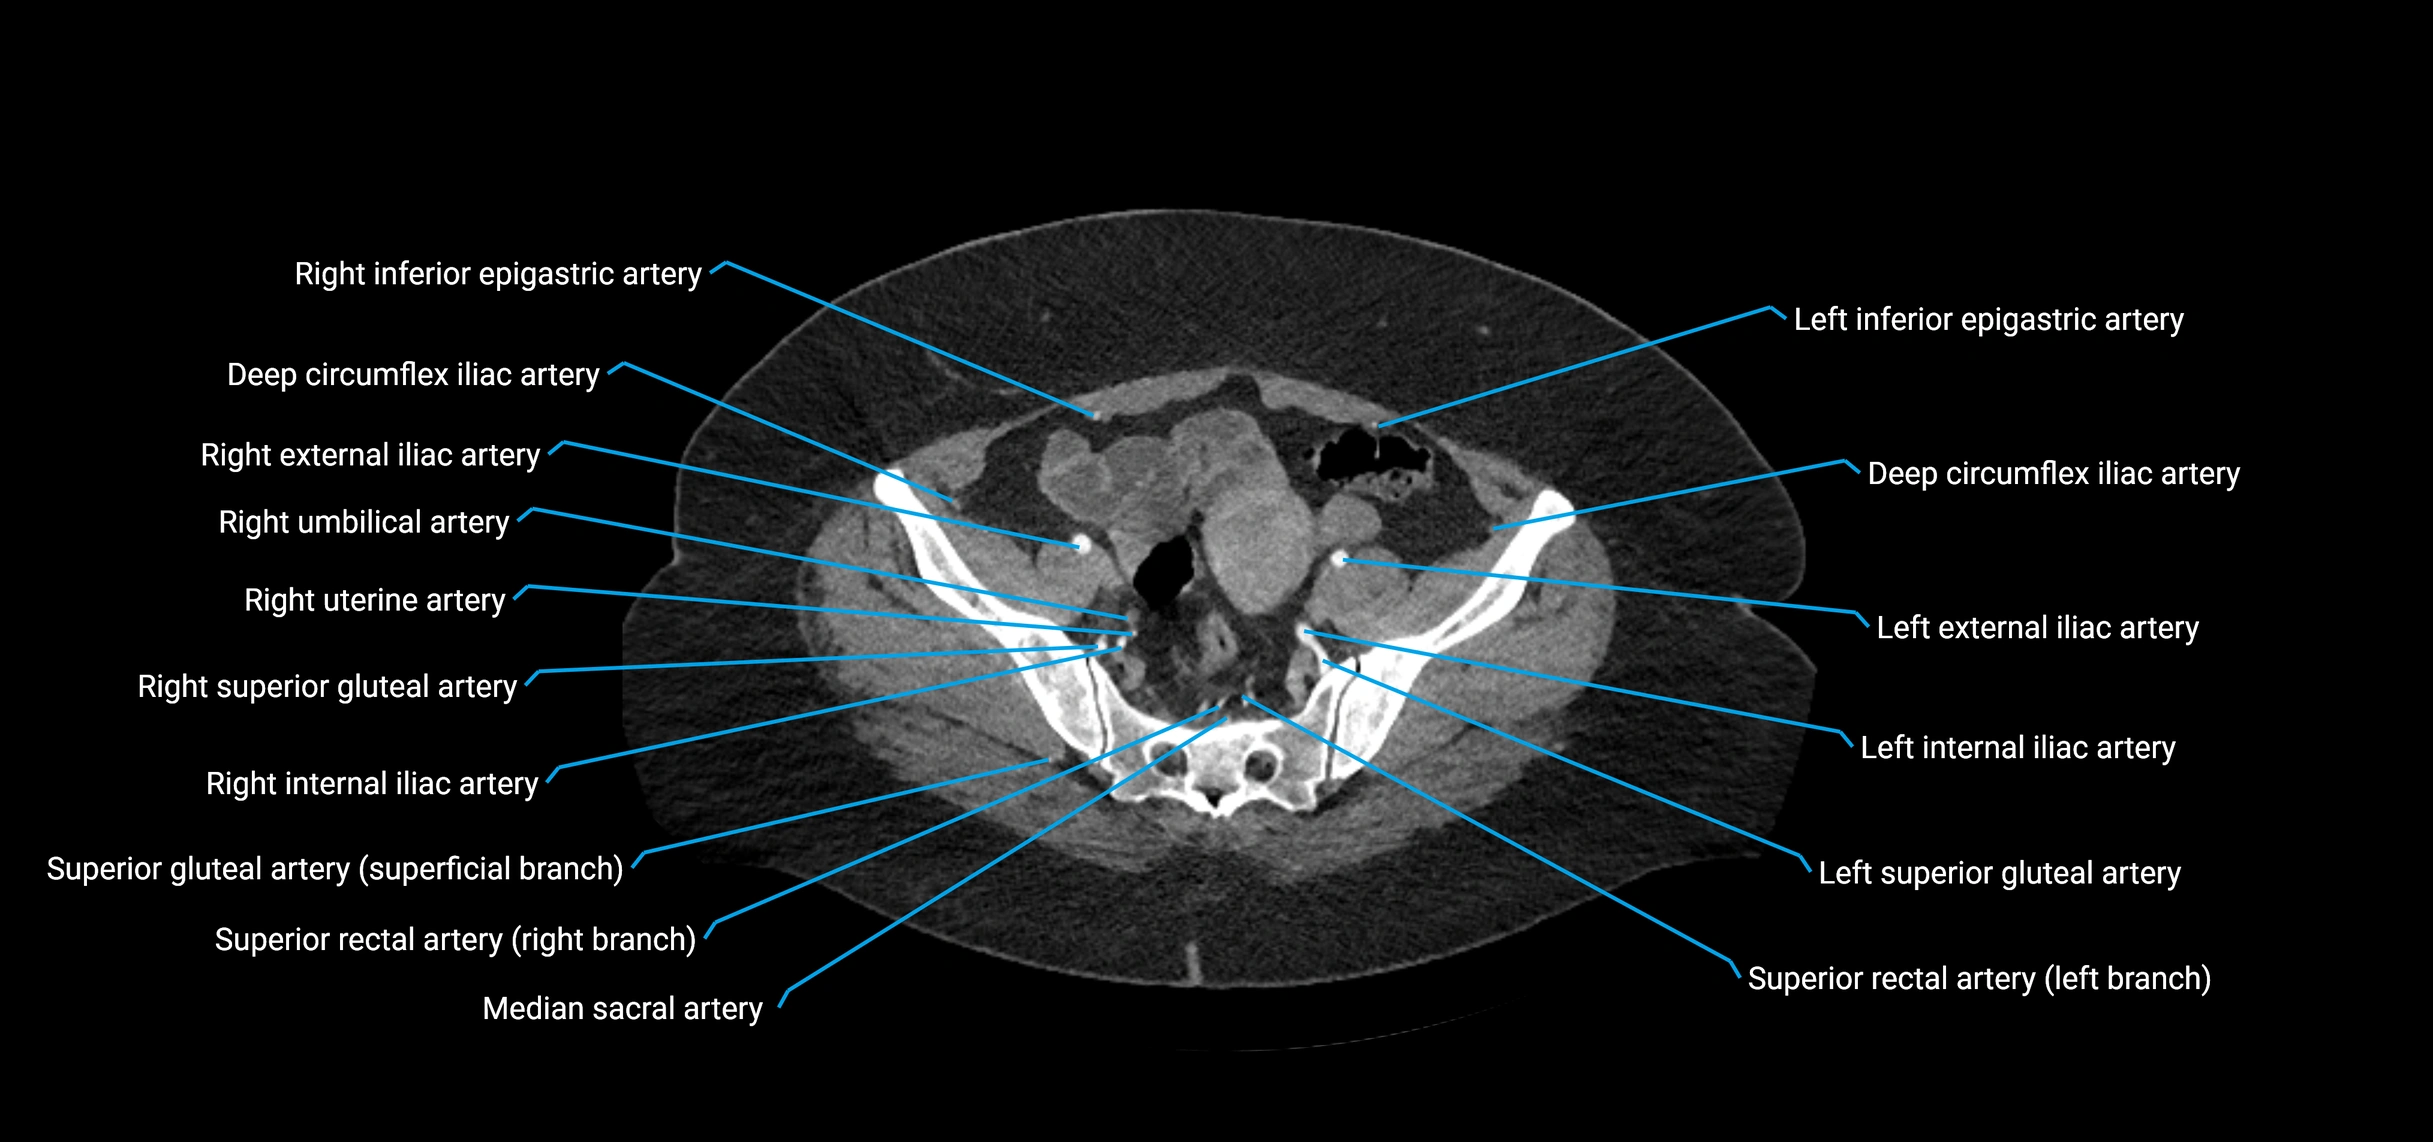

CT Appearance

Non-contrast CT:

• Appears as a tubular soft tissue structure anterior to vertebral bodies

• Calcified atherosclerotic plaques appear as hyperdense foci along the wall

• Useful for screening abdominal aortic aneurysm (AAA) size and mural calcification

Contrast-enhanced CT (CTA):

• Gold standard for abdominal aortic imaging

• Provides excellent detail of lumen, wall, aneurysm, thrombus, and branch vessels

• Multiplanar and 3D reconstructions help in aneurysm measurement, stent graft planning, and dissection evaluation

• Detects acute rupture, traumatic injury, or occlusion with high sensitivity

CT images

image